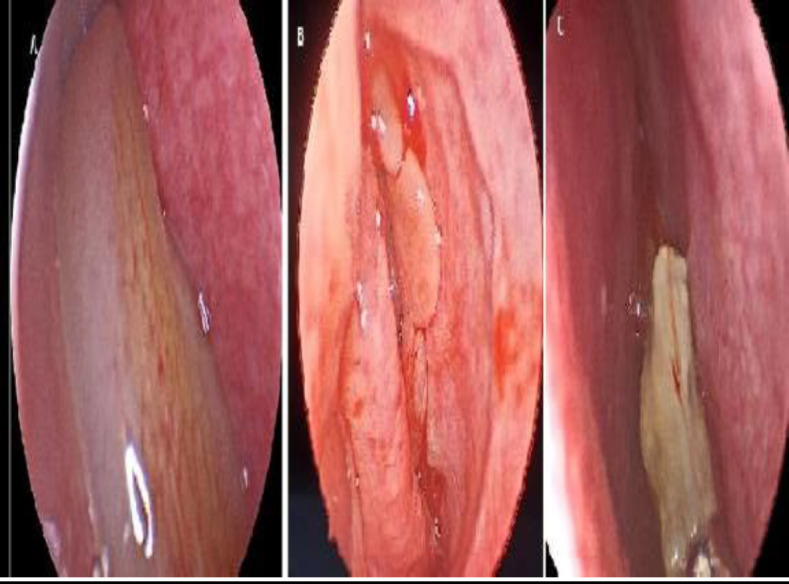

Results: In pediatric patients, the most common inflammatory pathology was antrochoanal polyps, followed by allergic fungal sinusitis. On the other hand, chronic sinusitis without nasal polyps is the most common in adults, followed by antrochoanal polyps. The mean duration of clinical manifestations before diagnosis in pediatric patients was significantly shorter than that in adults (P=0.001). The most common symptoms in both pediatric and adult patients were anterior nasal discharge and nasal obstruction. Proptosis was significantly higher in pediatric group than in adult group (P=0.015). On computed tomography (CT), the most commonly affected sinus in both pediatric and adult patients was the maxillary sinus followed by the anterior ethmoid sinus. Bone expansion, erosion and involvement of adjacent structures were significantly higher in pediatric patients (P=0.028, 0.027 respectively).

Conclusion: Pediatric patients have a high incidence of antrochoanal polyps and allergic fungal sinusitis as unilateral inflammatory lesions. These lesions require surgical management. Inflammatory paranasal sinus lesions in pediatric patients have a shorter duration of clinical manifestations and a higher incidence of bone erosion and involvement of adjacent structures; therefore, early diagnosis and management prevent complications.